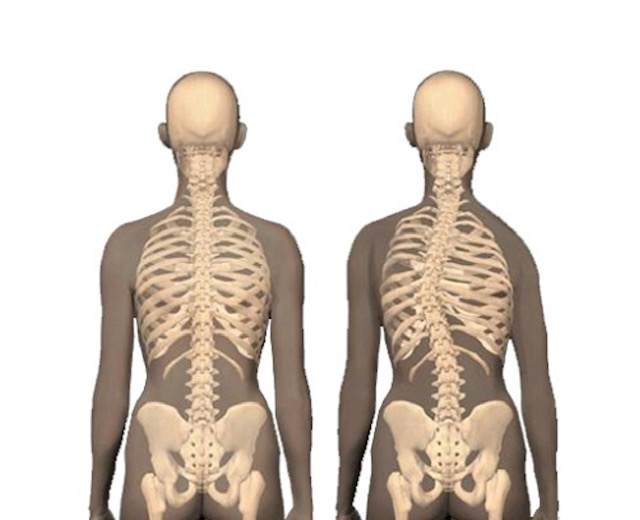

Mesela doğuştan kanal dar olabilir; enfeksiyonlar, tümörler, kırıklar, kırık sekelleri, fıtıklar bu hastalığa sebebiyet verebilir. Aynı zamanda omurgadaki bazı eğrilikler bu hastalığı meydana getirebilir. Bu eğrilikler gençlik çağından kalma eğrilikler olabildiği gibi sonradan çıkan eğrilikler de olabilir ve bunlarda karşımıza dar kanal veya Spinal Stenoz olarak çıkarlar.